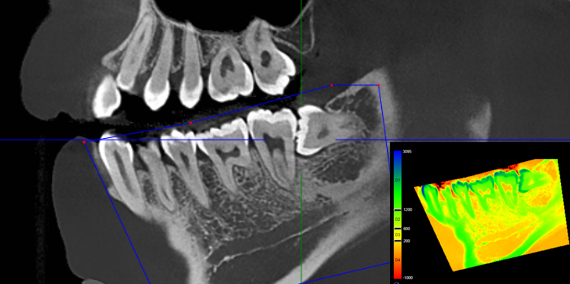

Airway Measurement

Automatically calculate the volume and the narrowest area of the airway in the form of chromatographic visualization.